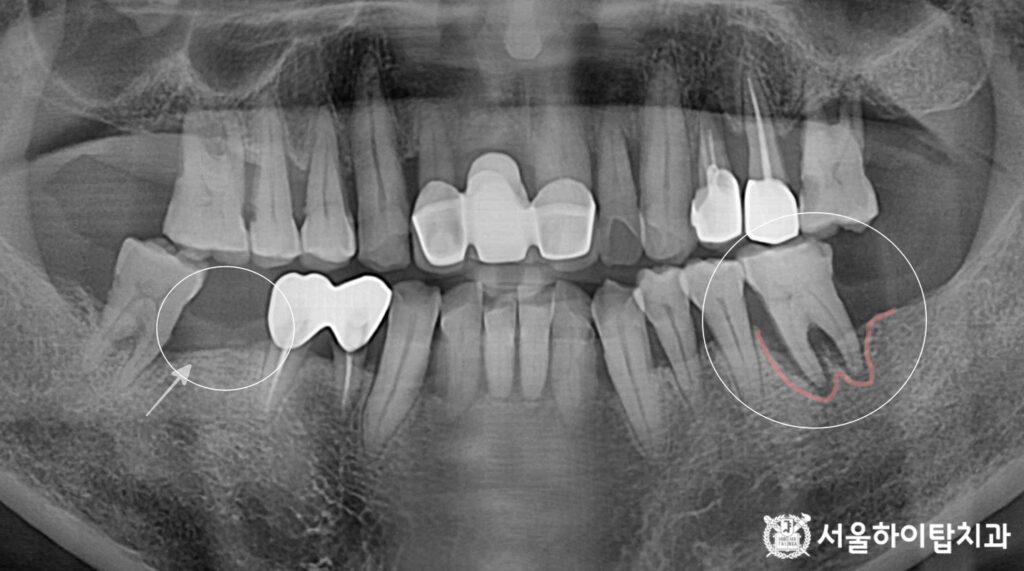

초진 파노라마 엑스레이를 확인해 보면,

앞서 간석오거리 치과 에서 말씀드린

문제들이 모두 확인됩니다.

사진 기준 왼쪽 부위는

오랜 기간 상실된 어금니,

반면 오른쪽 부위는 치주염으로 인해

치조골이 녹아내린 모습이 보입니다.

즉,

1) 장기간 방치된 무치악 부위,

2) 치주염으로 인한 골 소실 부위,

이 두가지 서로 다른 문제를

동시에 가지고 있는 것이죠.